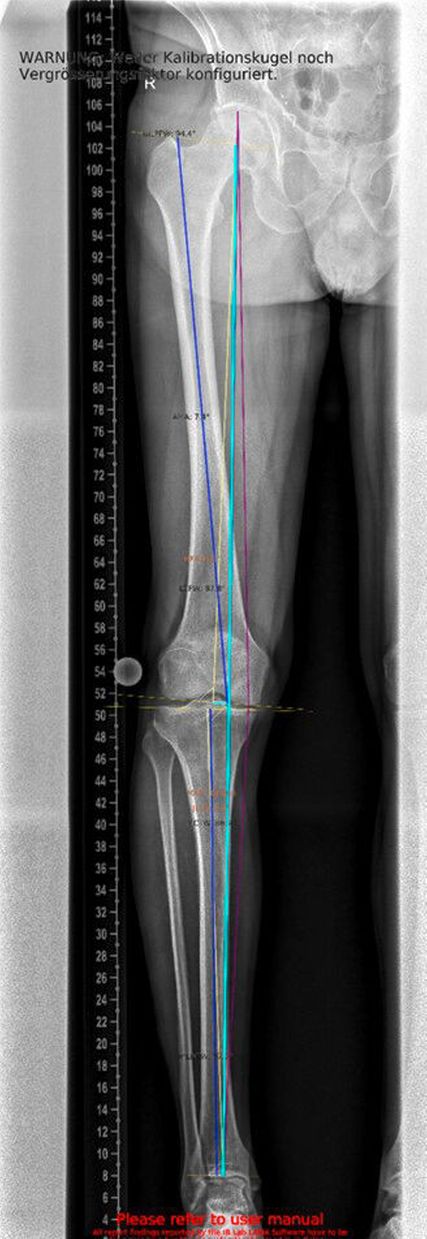

Ein weiterer kritischer Aspekt ist das Risiko für eine postarthroskopische Osteonekrose. Hinsichtlich der Pathogenese werden unterschiedliche Ursachen diskutiert: Zum einen gelten Meniskusläsionen als möglicher Hauptfaktor, zum anderen werden intraoperative Traumata, ein erhöhter intraartikulärer Druckanstieg während der Arthroskopie sowie veränderte Lastübertragungen nach partiellen Meniskusresektionen als ursächlich in Betracht gezogen.17 Nach partiellen Meniskusresektionen kann es zu einem signifikanten Anstieg subchondraler Druckspitzen kommen. Diese mechanische Überlastung fördert die Entstehung von Mikrofrakturen sowie subchondralen Perfusionsstörungen, die in der Folge in eine Osteonekrose übergehen können. Kobayashi et al. berichteten, dass bei 25% der Patient:innen nach partieller Meniskektomie eine juxtaartikuläre Osteonekrose auftrat, nach totaler Meniskektomie sogar bei 50%. Die Lokalisation der Nekrosen war variabel: In 16 von 32 Fällen manifestierten sie sich sowohl am tibialen als auch am femoralen Kondylus, in zehn Fällen isoliert am Tibiaplateau und in sechs Fällen ausschließlich am Femurkondylus. Nach medialer Teilmeniskektomie zeigte sich eine Prädisposition zur Manifestation im medialen femoralen Anteil, wohingegen nach lateraler Teilmeniskektomie überwiegend der laterale tibiale Anteil betroffen war.18 In der klinischen Praxis bedeutet dies, dass präoperativ eine alleinige MRT-Untersuchung des Meniskus nicht ausreicht. Vor allem bei klinischem Verdacht auf eine Achsenabweichung sollte eine Ganzbein-Standaufnahme zusätzlich durchgeführt werden. Nur so lässt sich die mechanische Beinachse zuverlässig beurteilen und in die Therapieplanung einbeziehen.

Ein 62-jähriger Patient stellte sich im März 2025 mit belastungsabhängigen Knieschmerzen rechts vor. Im MRT zeigte sich eine Läsion des medialen Meniskus, sodass in Zusammenschau mit dem positiven Meniskuszeichen in der klinischen Untersuchung eine partielle Meniskektomie durchgeführt wurde. Die postoperative Phase verlief zunächst unauffällig. Der Patient berichtete über ein beschwerdefreies Intervall von rund sieben Wochen. Anschließend entwickelten sich jedoch erneut zunehmende Schmerzen im rechten Kniegelenk, die eine erneute Vorstellung in der Spezialambulanz erforderlich machten. Er berichtete vor allem über belastungsabhängige Schmerzen im Bereich des medialen Kniegelenks. Daraufhin wurde ein Ganzbeinröntgen zur Beurteilung der Beinachse durchgeführt, hier zeigte sich eine varische Beinachse mit 5 Grad Varus (Abb.1). In der ergänzend durchgeführten MRT-Untersuchung konnte medialseitig eine ausgeprägte Nekrosezone am medialen Femurkondyl nachgewiesen werden (Abb.2). Schlussendlich wurde aufgrund dieses Befundes die Indikation zur Implantation einer medialen Hemischlittenprothese rechts gestellt, die schließlich im August 2025 komplikationslos durchgeführt wurde (Abb.3+4).